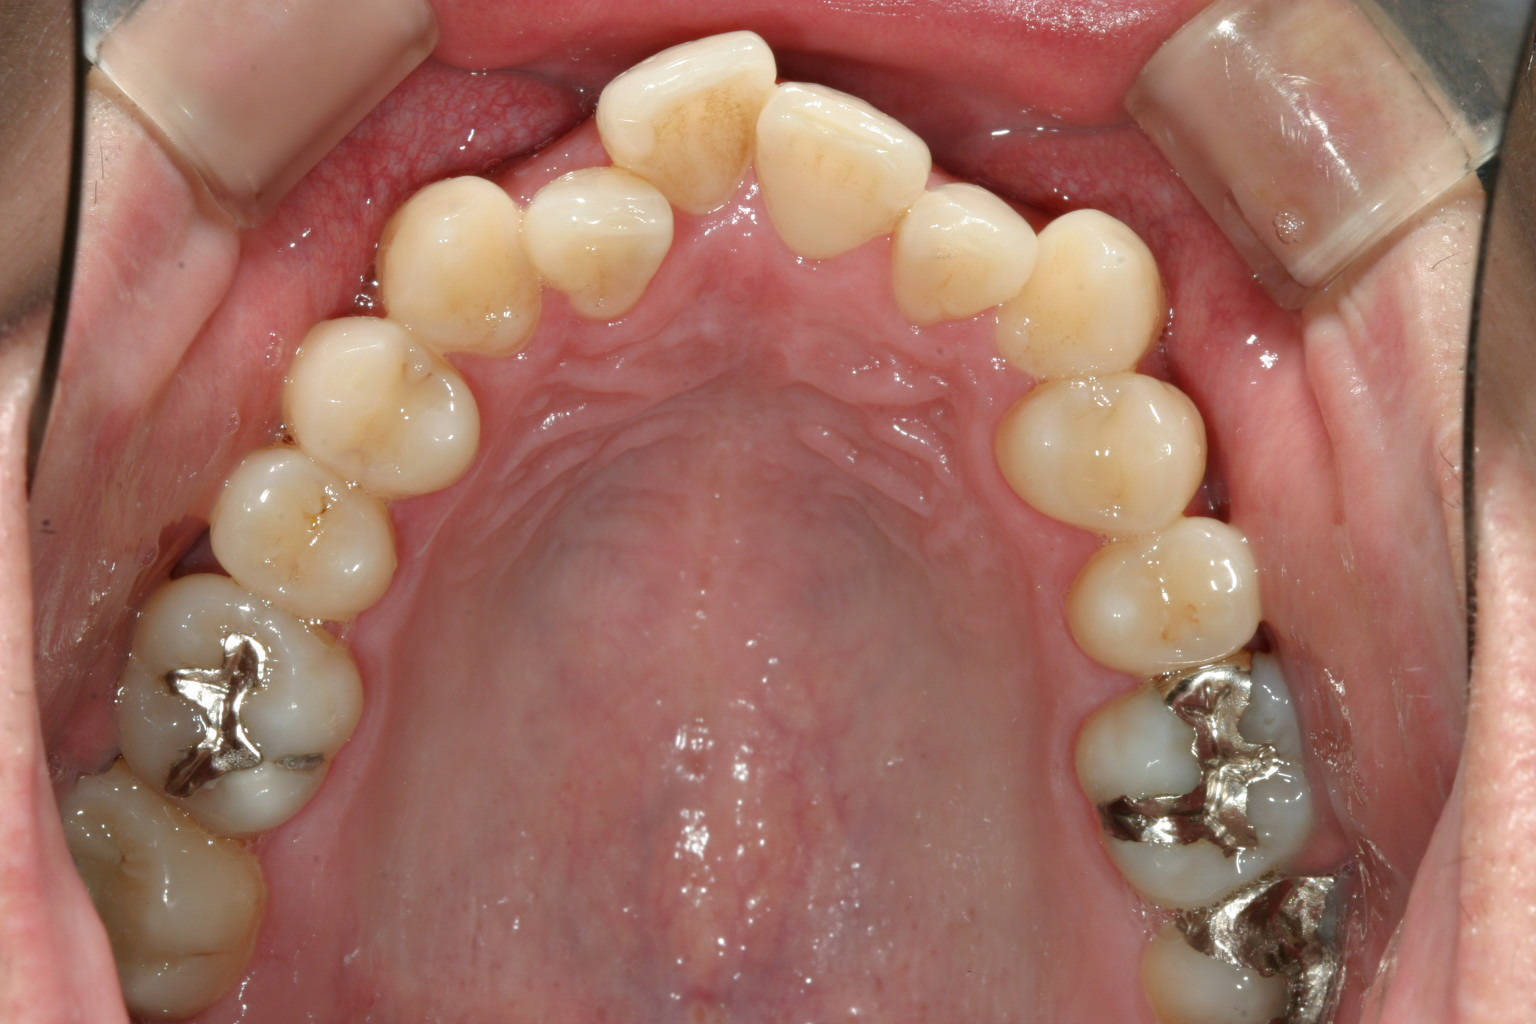

今回のケースは上下ともアーチ形状がV字の為スペースがなく4前歯が乱れている叢生にはよくあるケースです。

こういうケースの場合先ずアーチをU字に変える事から始まります。

インビザラインでアーチ形状を変えるにはマウスピースでは力が弱く少し時間を要します。

かみ合わせはさほど深く無い為、垂直的な大きな移動も無くアーチ形状さえ改善すればこの様に綺麗に配列しました。

又、アーチ形状をU字に変える事により出っ歯感も少し改善する事も出来ました。